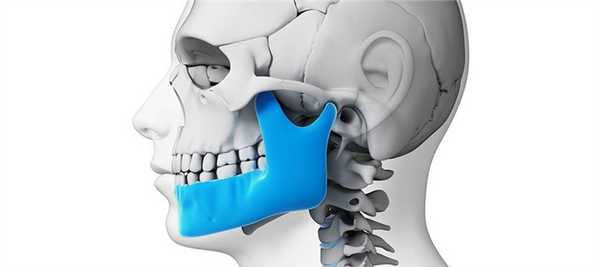

Анатомия височно-нижнечелюстного сустава

Височно-нижнечелюстной сустав (ВНЧС) — комбинированный парный сустав, образованный головками нижней челюсти и суставными бугорками (ямками), расположенными на височной кости. В полости ВНЧС имеются мениски — хрящевые пластинки, выполняющие роль прокладок и амортизаторов, а также обеспечивающие функцию сочленения. Благодаря этому височно-нижнечелюстной сустав способен выдерживать значительные нагрузки, возникающие при пережевывании пищи. По этой же причине ВНЧС имеет мощный связочный аппарат, укрепляющий и стабилизирующий сочленение.